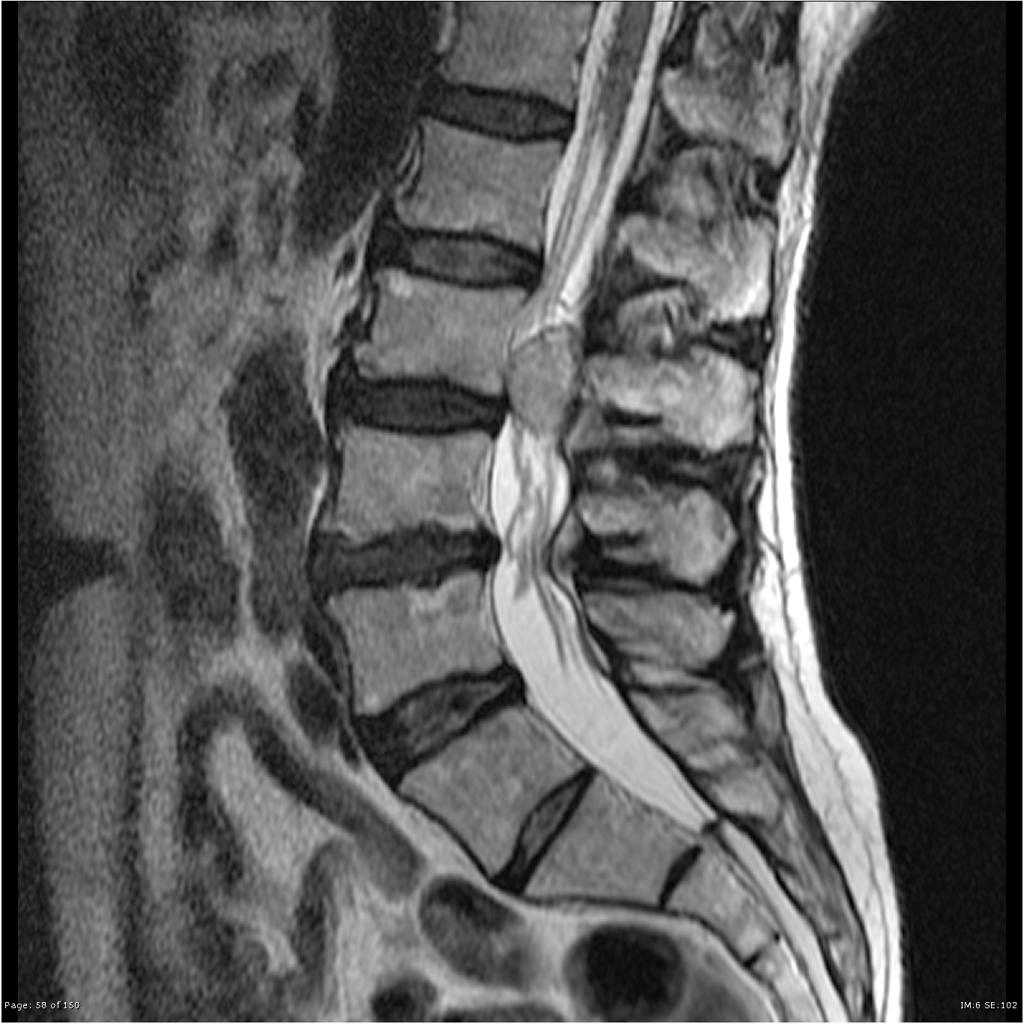

• IRM

• T1 : masse lobulée bien limitée, iso, hypo-intense

• Rehaussée après Gado

• T2 : hyper-intense + dépôts d’hémosidérine

• Aspect ponctué : vaisseaux intra-tumoraux (flow voids)

• Images serpigineuses péri-tumorales